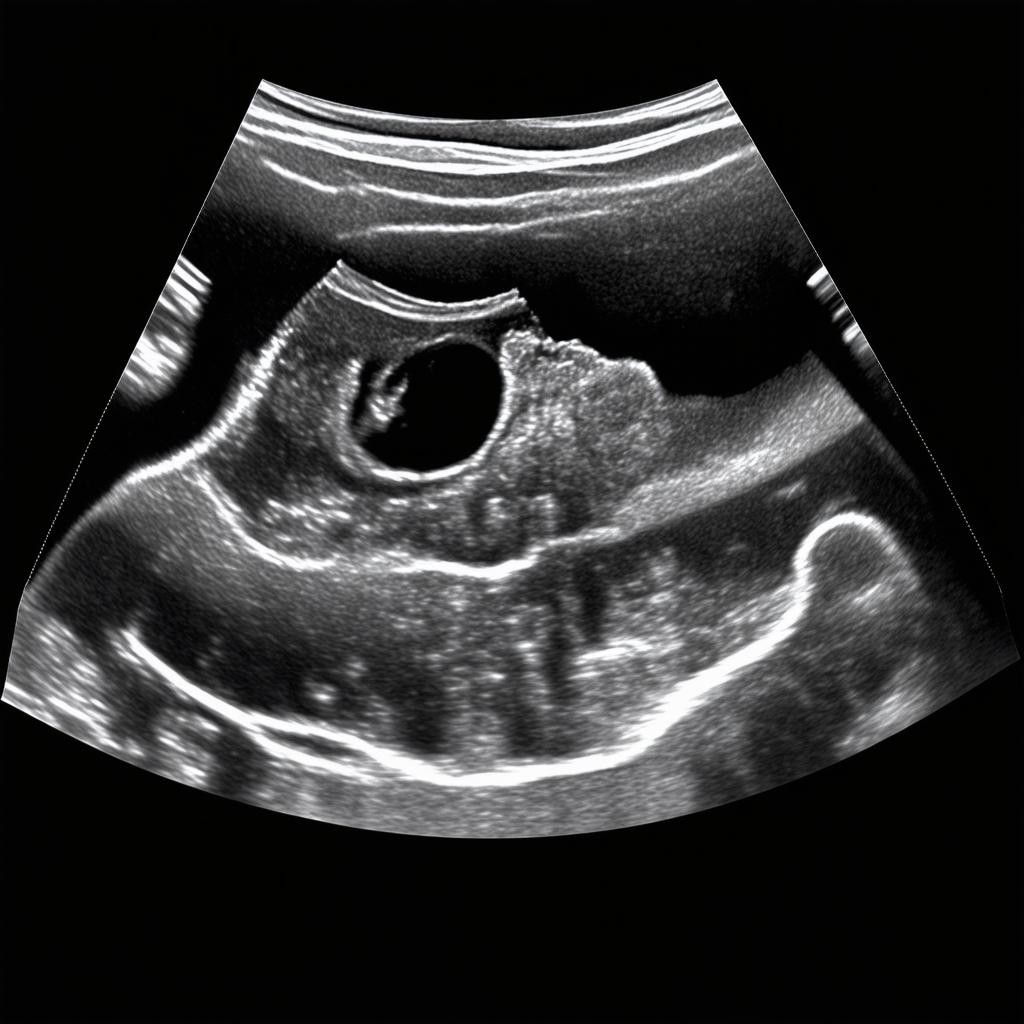

На экране визуализируется полость матки с плодным яйцом, внутри которого четко определяется эмбрион. Его внешний вид меняется: исчезает хвостик, начинается формирование конечностей. Специалист фокусируется на нескольких обязательных параметрах. Первый и главный — подтверждение сердечной деятельности. Сердце эмбриона, разделенное на камеры, совершает от 110 до 160 ударов в минуту, что является надежным маркером его жизнеспособности.

Второй критически важный показатель — копчико-теменной размер (КТР). Это длина эмбриона от головы до копчика, которая на 8 неделе в норме составляет примерно 14-20 мм. Данное измерение является наиболее точным для определения срока гестации. Параллельно врач оценивает состояние желточного мешка, который выполняет питательную и кроветворную функцию, а также структуру хориона — будущей плаценты. Любые отклонения в размерах или структуре этих образований тщательно документируются.